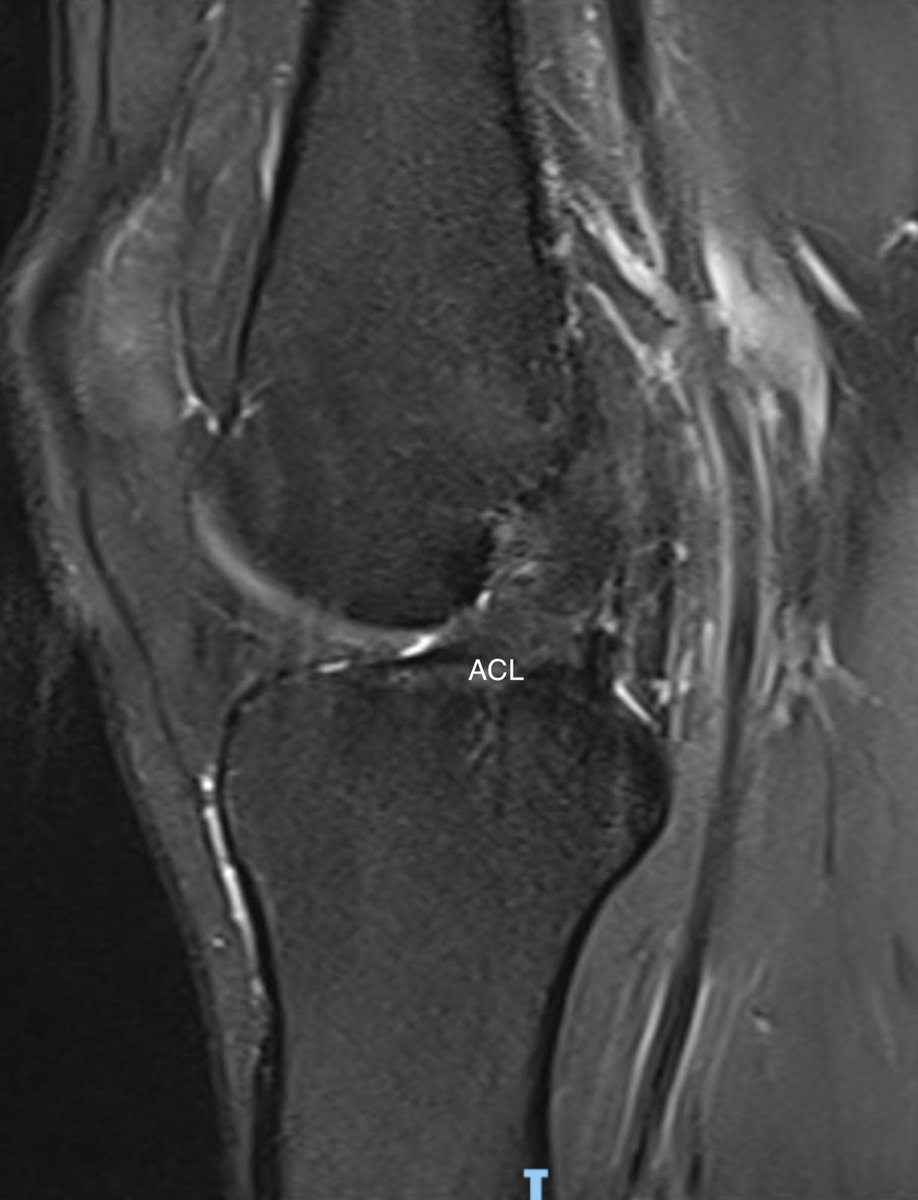

Consent ✅

Relevant case with respect to the 'healing' ACL & conservative management of ACL rupture debate

Footballer, twist, 'pop' & rapid onset swelling 2 years ago

Returned to football but struggled with sensation of imminent giving way / instability esp on change of direction

Few buckling episodes

Exam - increased travel on Lachman's testing, but firm-ish end point

MRI - healed ACL (thickened / scarred / in continuity)

So radiological healing definitely occurs, but doesn't necessarily tally with functional recovery